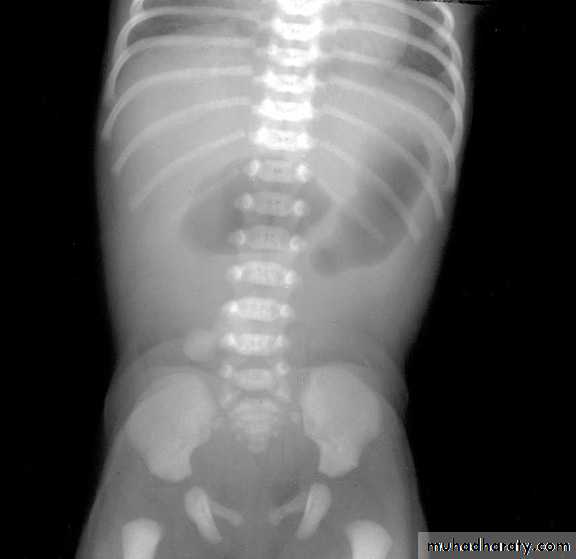

X-rays

Multiple dilated loops, air-fluid levels

Barium enema: microcolon